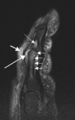

Magnetic resonance image of the index finger in psoriatic arthritis (mutilans form). Shown is a T2 weighted fat suppressed sagittal image. Focal increased signal (probable erosion) is seen at the base of the middle phalanx (long thin arrow). There is synovitis at the proximal interphalangeal joint (long thick arrow) plus increased signal in the overlying soft tissues indicating oedema (short thick arrow). There is also diffuse bone oedema (short thin arrows) involving the head of the proximal phalanx and extending distally down the shaft.